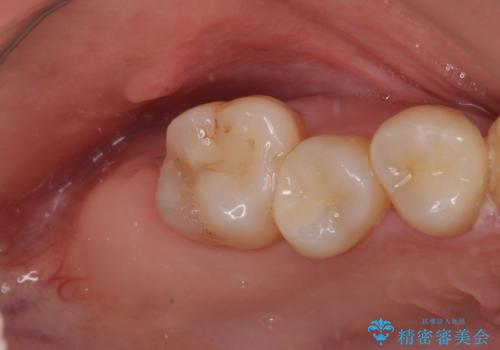

抜歯後に不快感は消失したのですが、手前の歯にあるむし歯が痛み出してきたため、セラミックインレーにて修復治療を並行して行いました。